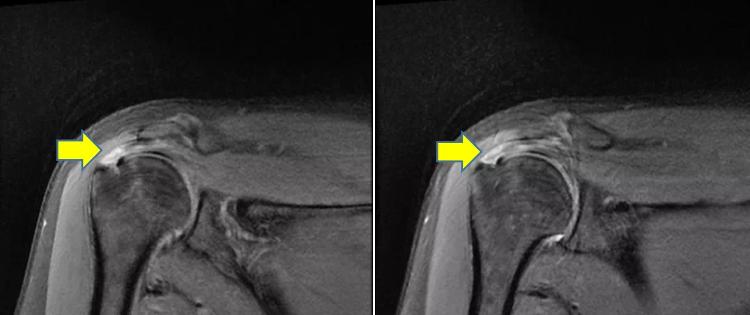

术前磁共振:

1.右侧肩袖(冈上肌腱)损伤

2.右侧肱骨大结节骨髓水肿

3.右肩关节间隙、肩峰下滑囊、喙突下滑囊少量积液。

术后3月行肩关节磁共振复查:冈上肌腱走形正常。肩袖损伤完美治愈。